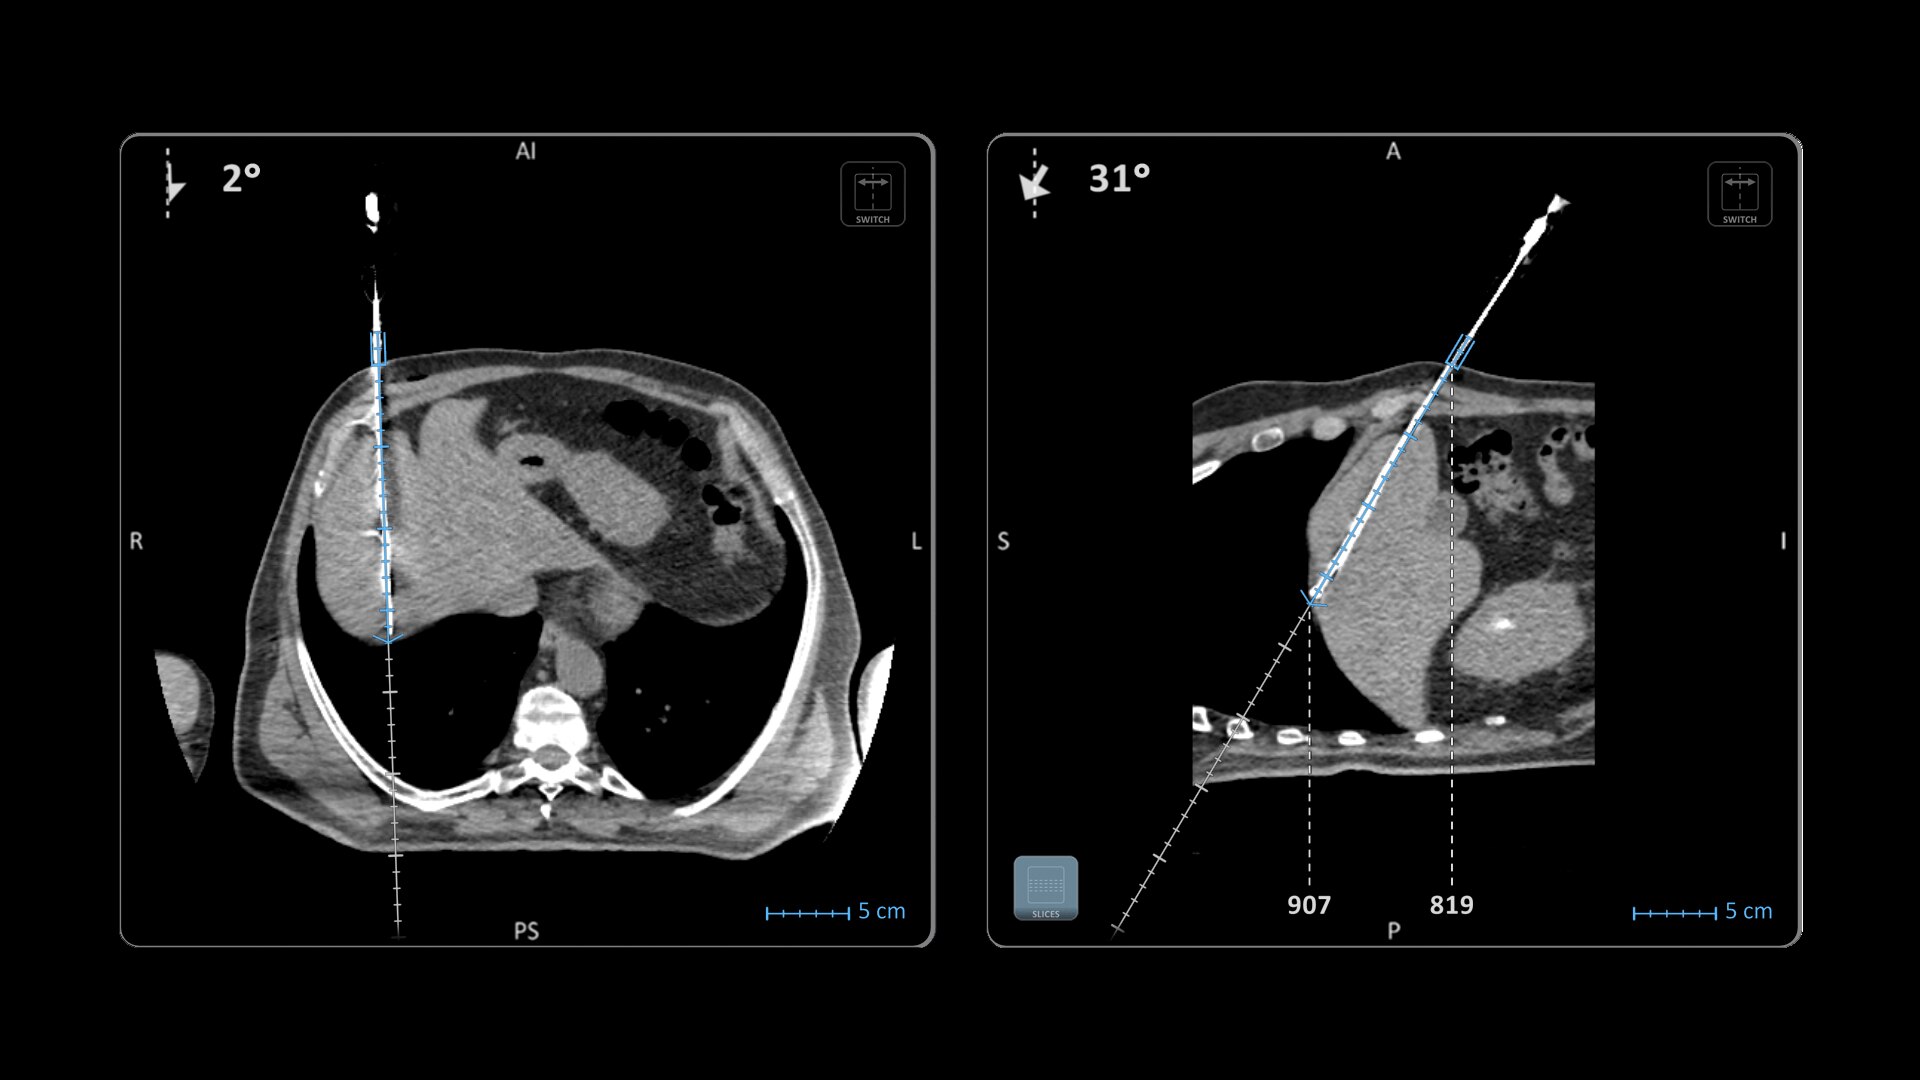

Automatizzando la ricostruzione SPECT/TC, SmartConsole semplifica il flusso di lavoro per protocolli ibridi e quantitativi complessi e consente ai tecnici di esaminare i risultati direttamente sulla console dello scanner. Inoltre, permette ai medici di rivedere le scansioni da remoto dai dispositivi mobili. Possono così modificare le impostazioni di elaborazione e avviare l'elaborazione dell'esame in qualsiasi momento e da qualsiasi posizione attraverso una LAN o una WAN*.

SmartConsole garantisce un notevole miglioramento della produttività. Ora un medico può fornire il proprio input da remoto. Per esempio è possibile esaminare una scansione ossea "Whole-Body" direttamente sul tablet o su un altro dispositivo mobile e definire i limiti dell'intervallo di scansione necessari da qualsiasi posizione.